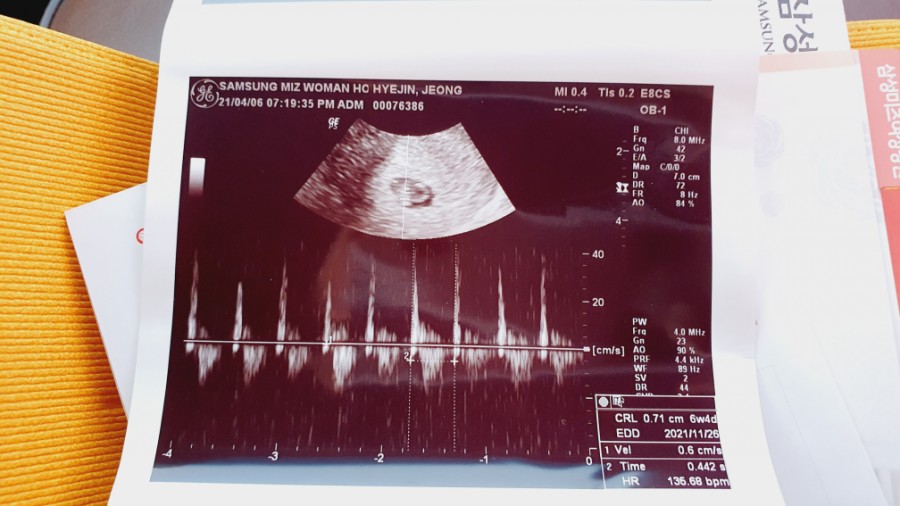

임신 6주차 아기의 심장 소리를 듣고 신기하고 감동적인 기쁨에 젖었다.그냥 신기해. 심장 소리를 내도 아직 내 안에 아기가 있다는 실감이 안 나.나중에 얘가 동그랗게 클 거라고 생각하니까 그것도 신기하다

심장 소리를 듣고 산전 검사를 했다.

심음을 듣고 모자수첩을 받아 들었다